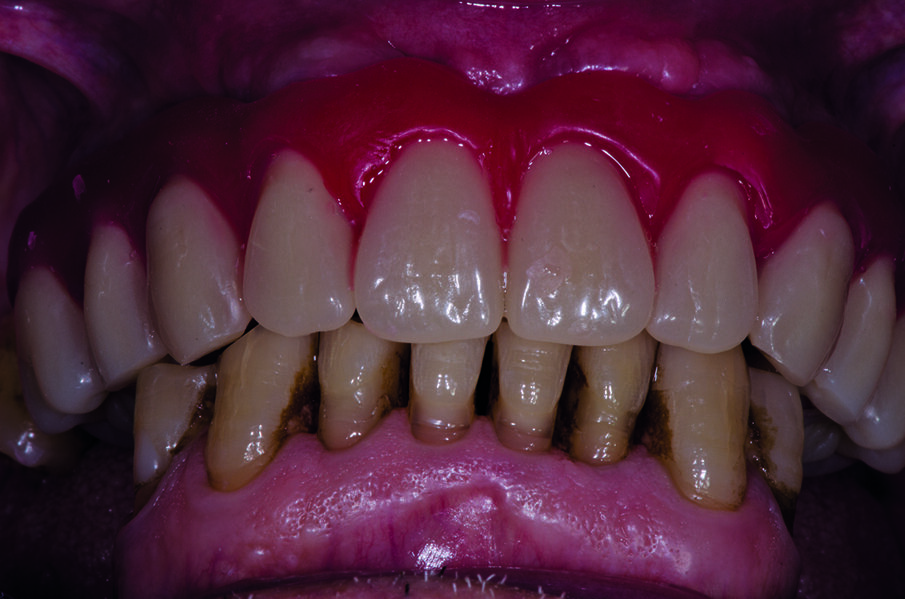

Dopo la terapia chirurgica, si inserisce una protesi totale provvisoria, che il paziente porterà per 6 mesi (Fig. 4b). Dopo i 6 mesi si monta la barra e la protesi totale superiore (Figg. 5, 6), che oltre a migliorare la masticazione e la fonetica del paziente, supporterà anche i tessuti molli, labbro, guancia, ridando al paziente un aspetto del sorriso giovanile e un supporto dei tessuti molli orali delle labbra, delle guance e delle rughe geniene (Figg. 7, 8). Il paziente viene inserito in un piano di mantenimento con un follow-up ogni 3 mesi (Fig. 9).

Per il trattamento di igiene orale domiciliare e professionale è importante prevenire mucosite e perimplantite, Si è rimotivato il paziente a corretti stili di vita di igiene orale secondo l’approccio tailor-made, personalizzato e condiviso con il paziente, sia per l’igiene domiciliare che per la terapia parodontale non chirurgica, implementandola con sedute di fototerapia Bioptron (Zepter).

Follow-up e igiene domiciliare

Documentiamo fotograficamente il cavo orale. Abbiamo mostrato al paziente, in real time, al fine di motivarlo a un più efficace controllo di placca domiciliare, i siti maggiormente interessati dall’accumulo di placca nel cavo orale, compresi, il dorso della lingua e gli spazi interprossimali e la barra implantare con l’aiuto del rilevatore di placca alla fluorescina Plac-o-Tect (Directa) (Fig. 10). Scegliamo per il paziente l’utilizzo corretto degli strumenti di igiene orale domiciliare – spazzolino e scovolino – più idonei alle sue esigenze strutturali, tissutali e anatomiche, alla manualità e alla predisposizione caratteriale alle differenti tecnologie manuali o meccaniche, come da tailored brushing method (Nardi et al., J Biomed, 2016).